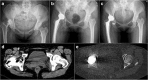

Results: A significantly higher frequency of protruded screws (24.8% vs 0), anterior overhang of acetabular components (30.8% vs 4.0%), and increased leg lengthening (3.6 [2.0-6.8] vs 0.5 [0-1.8]) was found in the dysplastic group (all p values < 0.05). However, the femoral offset and inclination and anteversion of acetabular components between the groups did not differ significantly. No difference in the prevalence of iliopsoas tendonitis was found between the groups. A new cause of iliopsoas tendonitis following total hip arthroplasty was detected in the dysplastic group. The iliopsoas tendonitis was irritated by an instable artificial femoral head.

Conclusions: The dysplastic hips did not present a higher incidence of postoperative iliopsoas tendonitis in this study. Iliopsoas tendonitis could be somewhat prevented by smaller size of acetabular components and soft tissue release in dysplastic hips, but irritated by an instable artificial femoral head.